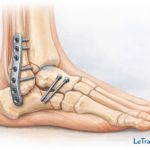

Chirurgie (arthroscopie ou décompression)

- Réservée aux cas graves ou aux échecs des traitements conservateurs.

- L’arthroscopie permet d’agir sur des lésions profondes.

👉 En savoir plus sur l’arthroscopie ici